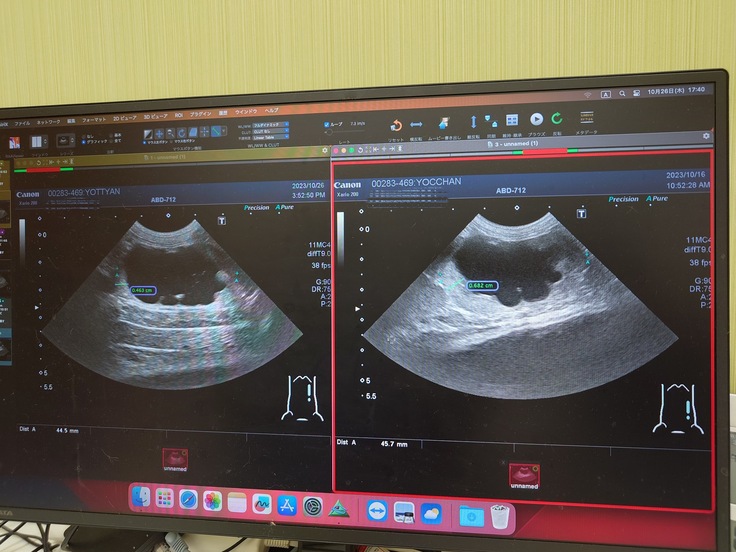

かかりつけの病院でエコー検査をしてもらったら寄生虫でも真菌でもない、別の2つ大きな病気が見つかりました。

◆1つ目は何かしらの原因で尿管が詰まっていて左側の腎臓と腎盂が肥大して左側の腎臓がほぼ機能していない状態。

🐈エコー検査で腎臓と腎盂の肥大、脾臓も肥大していることが分かりました🐈